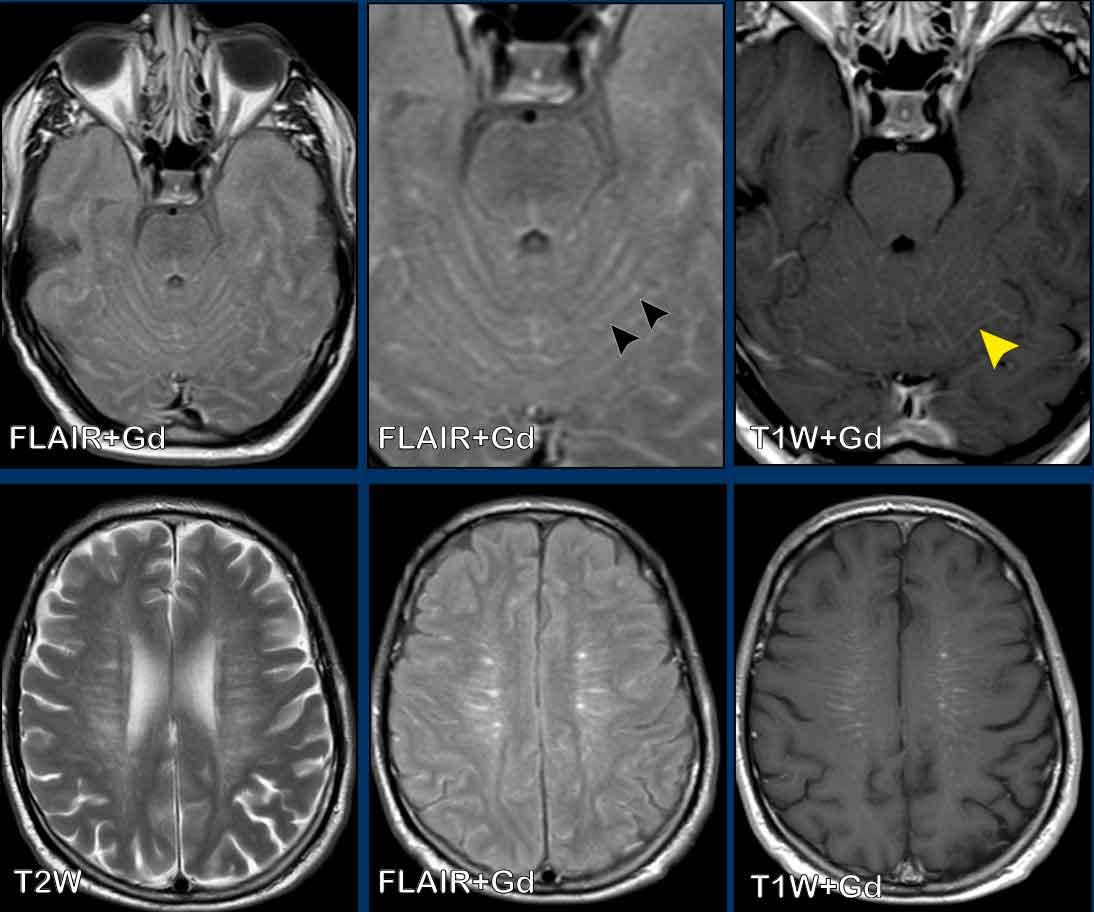

Các hình ảnh này của một bệnh nhân nam 58 tuổi nhập viện với triệu chứng đau đầu ở tư thế ngồi và đứng.

Hình ảnh

Có ngấm thuốc màng cứng đều đặn ở cả khoang trên lều và dưới lều.

Lưu ý các não thất nhỏ.

Tiếp tục với các hình ảnh mặt phẳng đứng dọc…

Các dấu hiệu khá tinh tế, nhưng bao gồm:

- Sa thấp trung não với giảm khoảng cách cầu-vú, xóa bể trên hố yên, dẹt phần trước cầu não và gập góc thân não tại chỗ nối sọ-cổ.

- Vùng dưới đồi gập qua mặt lưng hố yên, tuyến yên hơi phì đại (vòng tròn trắng).

- Liên hợp đồi thị bị hạ thấp; phần sau thể chai bị hạ thấp (dấu hiệu “dương vật rũ”). Lưu ý sự dẹt của bể trên tiểu não.

- Trong trường hợp này, amygdale ở vị trí bình thường và không có thoát vị (vòng tròn vàng).

Kết luận: các dấu hiệu điển hình của hạ áp lực nội sọ.

Hình 2

Sau điều trị bằng miếng vá máu ngoài màng cứng không định vị mục tiêu, não và thân não đã trở về vị trí bình thường với sự bình thường hóa cấu hình các bể và não thất IV.

Các hình ảnh này của một bệnh nhân nam 44 tuổi, nhập viện với triệu chứng đau đầu kéo dài, tăng lên khi cúi người về phía trước.

Chuỗi xung T2W cho thấy tụ dịch dưới màng cứng hai bên nhỏ (đầu mũi tên).

Sau khi tiêm gadolinium có ngấm thuốc màng cứng đều đặn.

Có sự ứ máu các cấu trúc tĩnh mạch, thể hiện ở xoang dọc trên (đầu mũi tên), xoang thẳng và hợp lưu xoang.

Có sự dịch chuyển xuống dưới của thân não với rút ngắn khoảng cách cầu-vú, dẹt cầu não và gập góc thân não tại chỗ nối sọ-cổ.

Đám rối tĩnh mạch trong khoang ngoài màng cứng phía trước cổ bị giãn rộng.

Kết luận

Các dấu hiệu này điển hình cho hạ áp lực nội sọ.

Bệnh nhân sau đó được chẩn đoán mắc rối loạn mô liên kết.